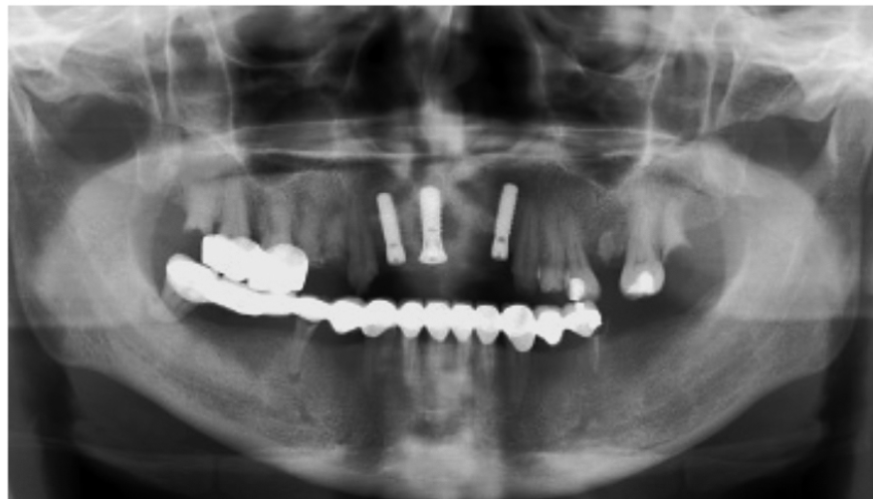

图1 术前全景片显示A1B2缺失

图2 术后全景片A1B2种植术后

首先在进行临床检查时,可以观察到缺牙区的宽度和厚度,用手指扪诊时前庭沟骨质没有明显的凹陷,这种情况可以拍摄牙片了解牙槽骨状况及与鼻腔的距离。由于牙片显示的范围有限,最好能够拍摄全景片了解邻近结构的情况,比如邻牙的情况、鼻腔底的距离,切牙孔的大小与位置等等。

(二)CBCT帮助准确判断

由于全景X线机设计的原因,前牙区必然会受到颈椎、咽腔重叠的影响,常常显示的影像不是很清楚,而且前牙区的水平失真率变化较大,有时候可以看见种植体形状发生改变。必要时可常规拍摄CBCT,以了解骨质高度、宽度以及骨质的密度的状况,有利于种植方案的确定以及植入角度的判断。